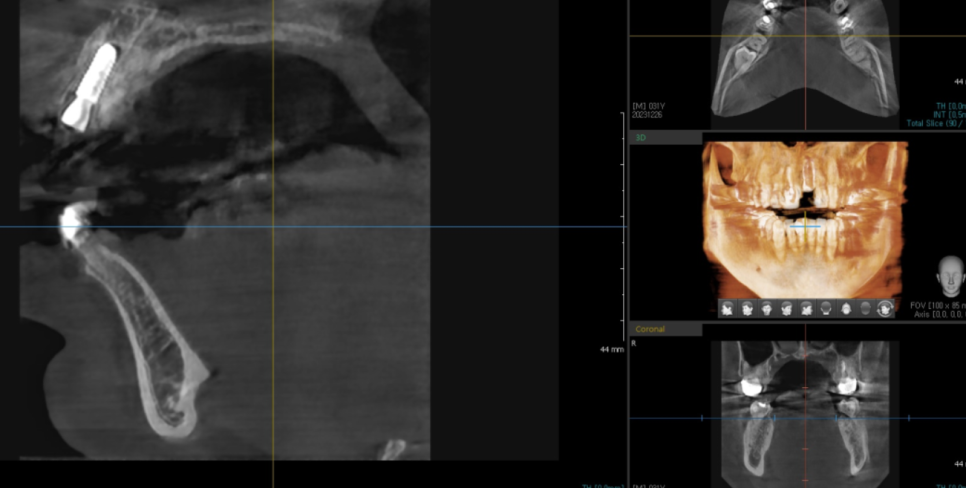

3d-ct를 사용하여

잔존 뼈를 확인

임플란트 깊이, 두께, 식립 각도 등을 예측

디지털 진료를 활용하여

안전하게 수술을 마무리하였습니다.